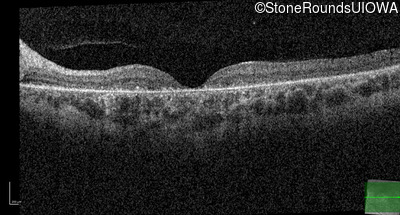

AR Stargardt Disease (IIA)

Age at visit: 15 years

This 15 year old female recalls not being able to see the black board in 2nd grade despite sitting in the 2nd row.

AR Stargardt Disease ABCA4 Val256Val GTG>GTT His1118Asp CAC>GAC AR